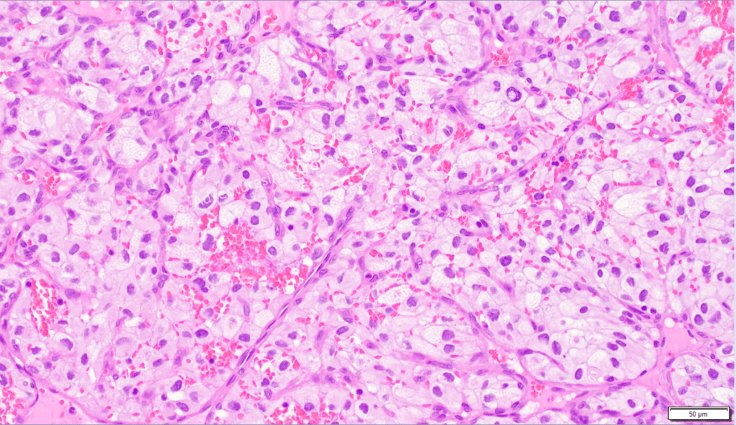

On gross examination, hemangioblastoma characteristically exhibits a yellow to yellow-orange color (similar to that of adipose tissue) due to the presence of lipid within the cytoplasm of neoplastic cells. On microscopic examination, the cells appear clear because the lipid that once filled the cytoplasm was washed out during tissue processing.

Hemangioblastoma usually arises within the cerebellum and represents one of the signature neoplasms commonly developed by persons with von Hippel Lindau (VHL) disease, which is, in addition to hemangioblastomas of the cerebellum as well as the retina, associated cysts of liver and pancreas, pheochromocytoma, and kidney tumors. The diagnosis that must be considered in the differential of hemangioblastoma, especially in VHL patients, is metastasis of the clear cell conventional subtype of Renal Cell Carcinoma (RCC). RCC is positive for Pax8 and CD10 immunostains, whereas hemangioblastoma is characteristically positive for Inhibin alpha.